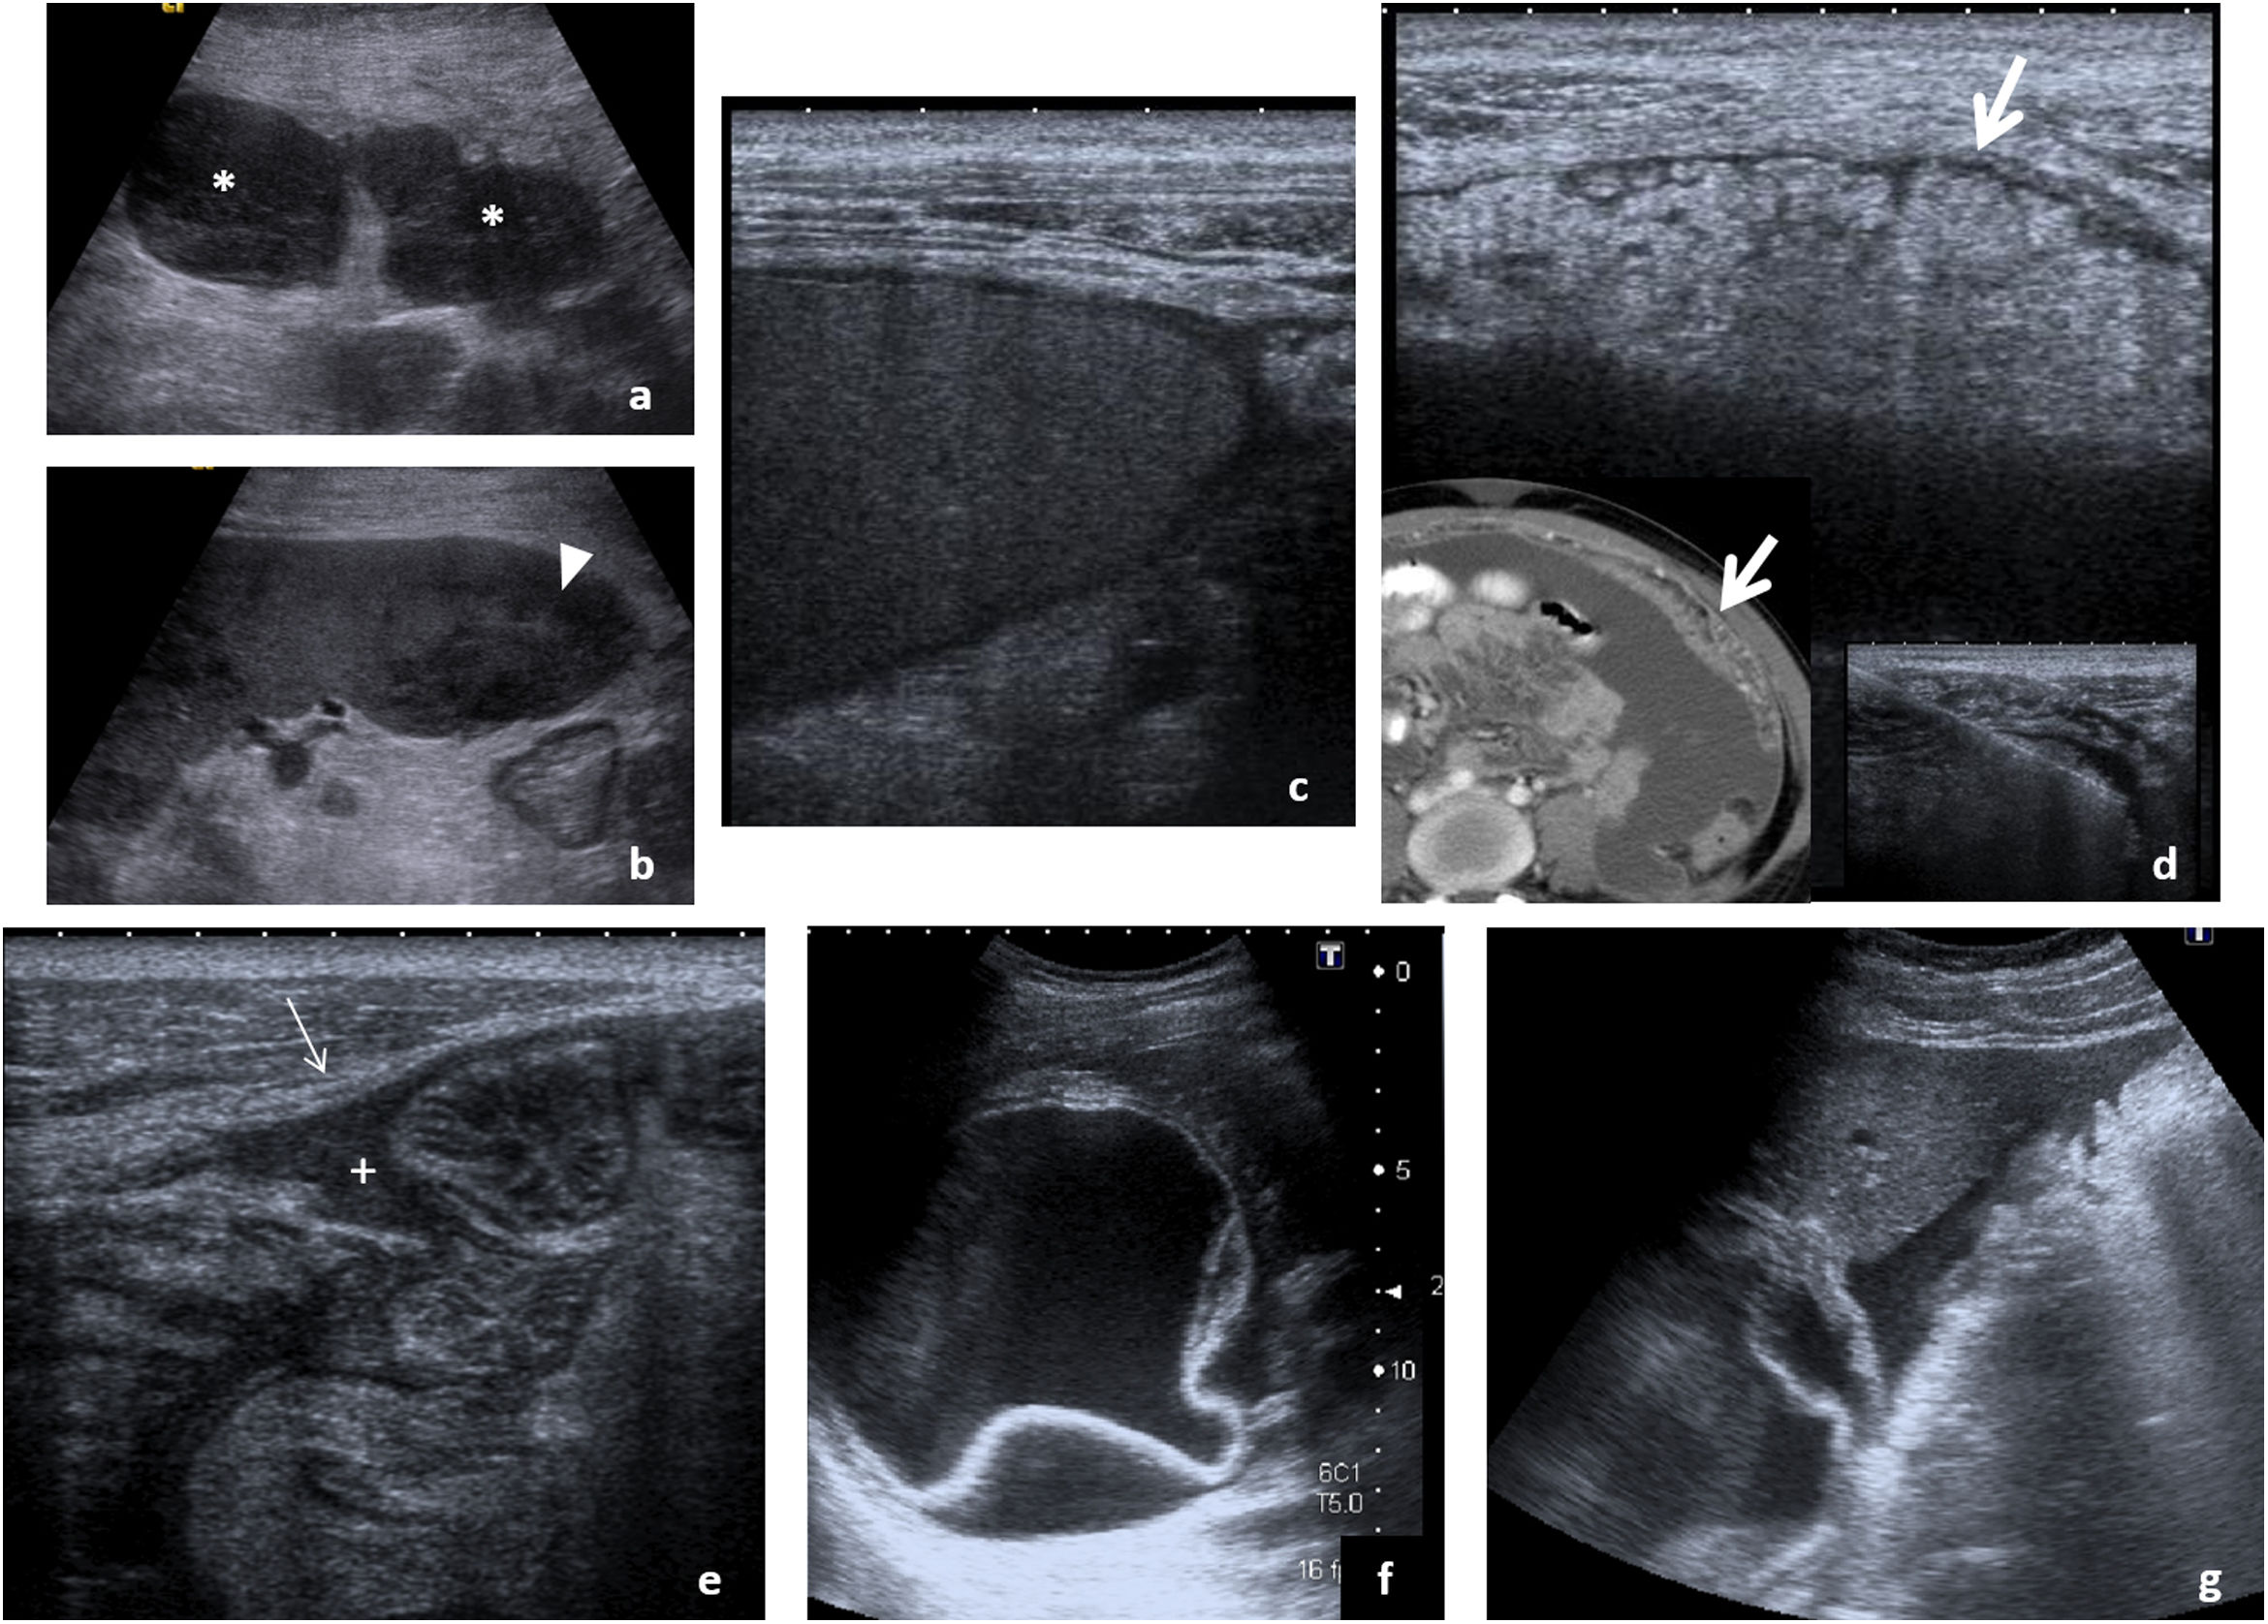

Se acompaña de adenopatías mesentéricas, periportales y paraaórticas superiores, a menudo con centro hipoecoico por necrosis (fig. 3A), y ocasionalmente calcificadas (generalmente no en fase activa). Forman conglomerados menos frecuentemente que otras entidades.

Afectación infecciosa del peritoneo. A-D) Hallazgos característicos de peritonitis tuberculosa en varios pacientes. Adenopatías mesentéricas (A) con centro hipoecoico por presencia de necrosis (*), afectación esplénica (B) con absceso en polo inferior del bazo (cabeza de flecha) y ascitis (C) con punteado ecogénico por material denso. Un dato significativo es el engrosamiento del epiplón mayor (flechas gruesas), que se aprecia con detalle en la ecografía (D), y se correlaciona con la imagen tomográfica mostrada en la esquina inferior izquierda. Plantea el diagnóstico diferencial con infiltración tumoral, por lo que precisa habitualmente de estudio histológico tras la obtención de una muestra que puede ser guiada ecográficamente como se aprecia en la imagen de la esquina inferior derecha. E-G) Peritonitis de otro origen. En el primer caso (E), paciente con cuadro de apendicitis aguda que se acompaña de discreta cantidad de líquido libre entre asas, con punteado ecogénico (+) y engrosamiento lineal del peritoneo parietal (flecha fina) que indica la presencia de peritonitis focal asociada. El segundo caso, peritonitis parasitaria en paciente con quiste hidatídico hepático (F) con membranas plegadas y presencia de líquido perihepático (G) que indica complicación del mismo con rotura y diseminación peritoneal del contenido.

La presencia de microabscesos en hígado y bazo (fig. 3B), la afectación de otros órganos abdominales (suprarrenales, páncreas o aparato genitourinario) y de localizaciones frecuentes fuera del abdomen como pulmón, hueso o sistema nervioso central orientan el diagnóstico6,15–19.

PeritoneoLa peritonitis tuberculosa es la manifestación más frecuente de la tuberculosis abdominal. Clásicamente se describen tres patrones: peritonitis húmeda, la más frecuente (90%), con ascitis de distribución libre o loculada, punteado ecogénico por alta densidad del líquido y engrosamiento peritoneal (fig. 3C); peritonitis seca, con escasa cantidad de líquido y adherencias completas o incompletas; y peritonitis fibrótica, con nódulos y masas mesentéricos y engrosamiento nodular del omento. La ecografía permite explorarlos con detalle y sirve de guía para la biopsia diagnóstica (fig. 3D). Descrita como la gran imitadora, su diagnóstico diferencial incluye la carcinomatosis peritoneal, el linfoma, la enfermedad de Crohn, el mesotelioma, el pseudomixoma peritoneal o la peritonitis piógena.

La peritonitis piógena (fig. 3E) es el resultado de la complicación de una infección abdominal generalmente de origen intestinal y puede derivar en abscesos, que a menudo requieren drenaje percutáneo guiado por ecografía. La peritonitis bacteriana espontánea es una complicación de cirrosis descompensada, a sospechar en caso de ascitis con fiebre o deterioro clínico. Su diagnóstico precisa paracentesis diagnóstica ecoguiada. Cabe mencionar las peritonitis parasitarias, que en nuestro medio suelen deberse a la rotura de un quiste hidatídico hepático (fig. 3F y G)32,33.